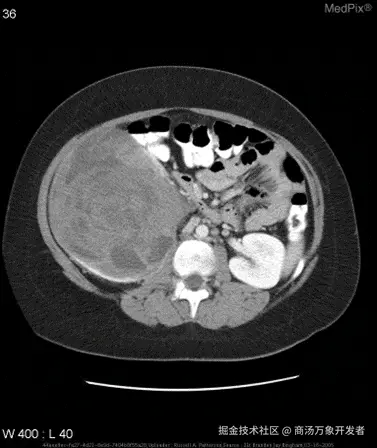

• 示例:针对如下影像,微调前后的输出

cd1aad943db53a3cdfaeb1883bfda041.png

微调前:

{

"query": "is the liver visible in the image?",

"true": "no",

"infer": "yes, the liver is visible in the image. it appears as a large, dark gray structure located in the upper left quadrant of the abdomen.",

"exact_score": 0,

"cosine_score": 0.3227266048281184

}

微调后:

"infer": "no",

"exact_score": 1,

"cosine_score": 1.0